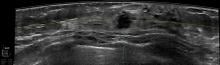

GE Healthcare introduced the new Logiq E9 with XDclear, a new general imaging ultrasound system, at RSNA 2012. Built from the acclaimed Logiq E9 platform, new features on the company’s premium product allow for increased penetration on large patients, improved clarity and diagnostic confidence.